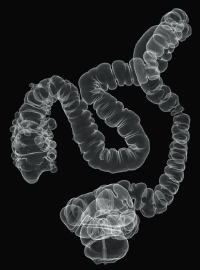

Colonic polyp